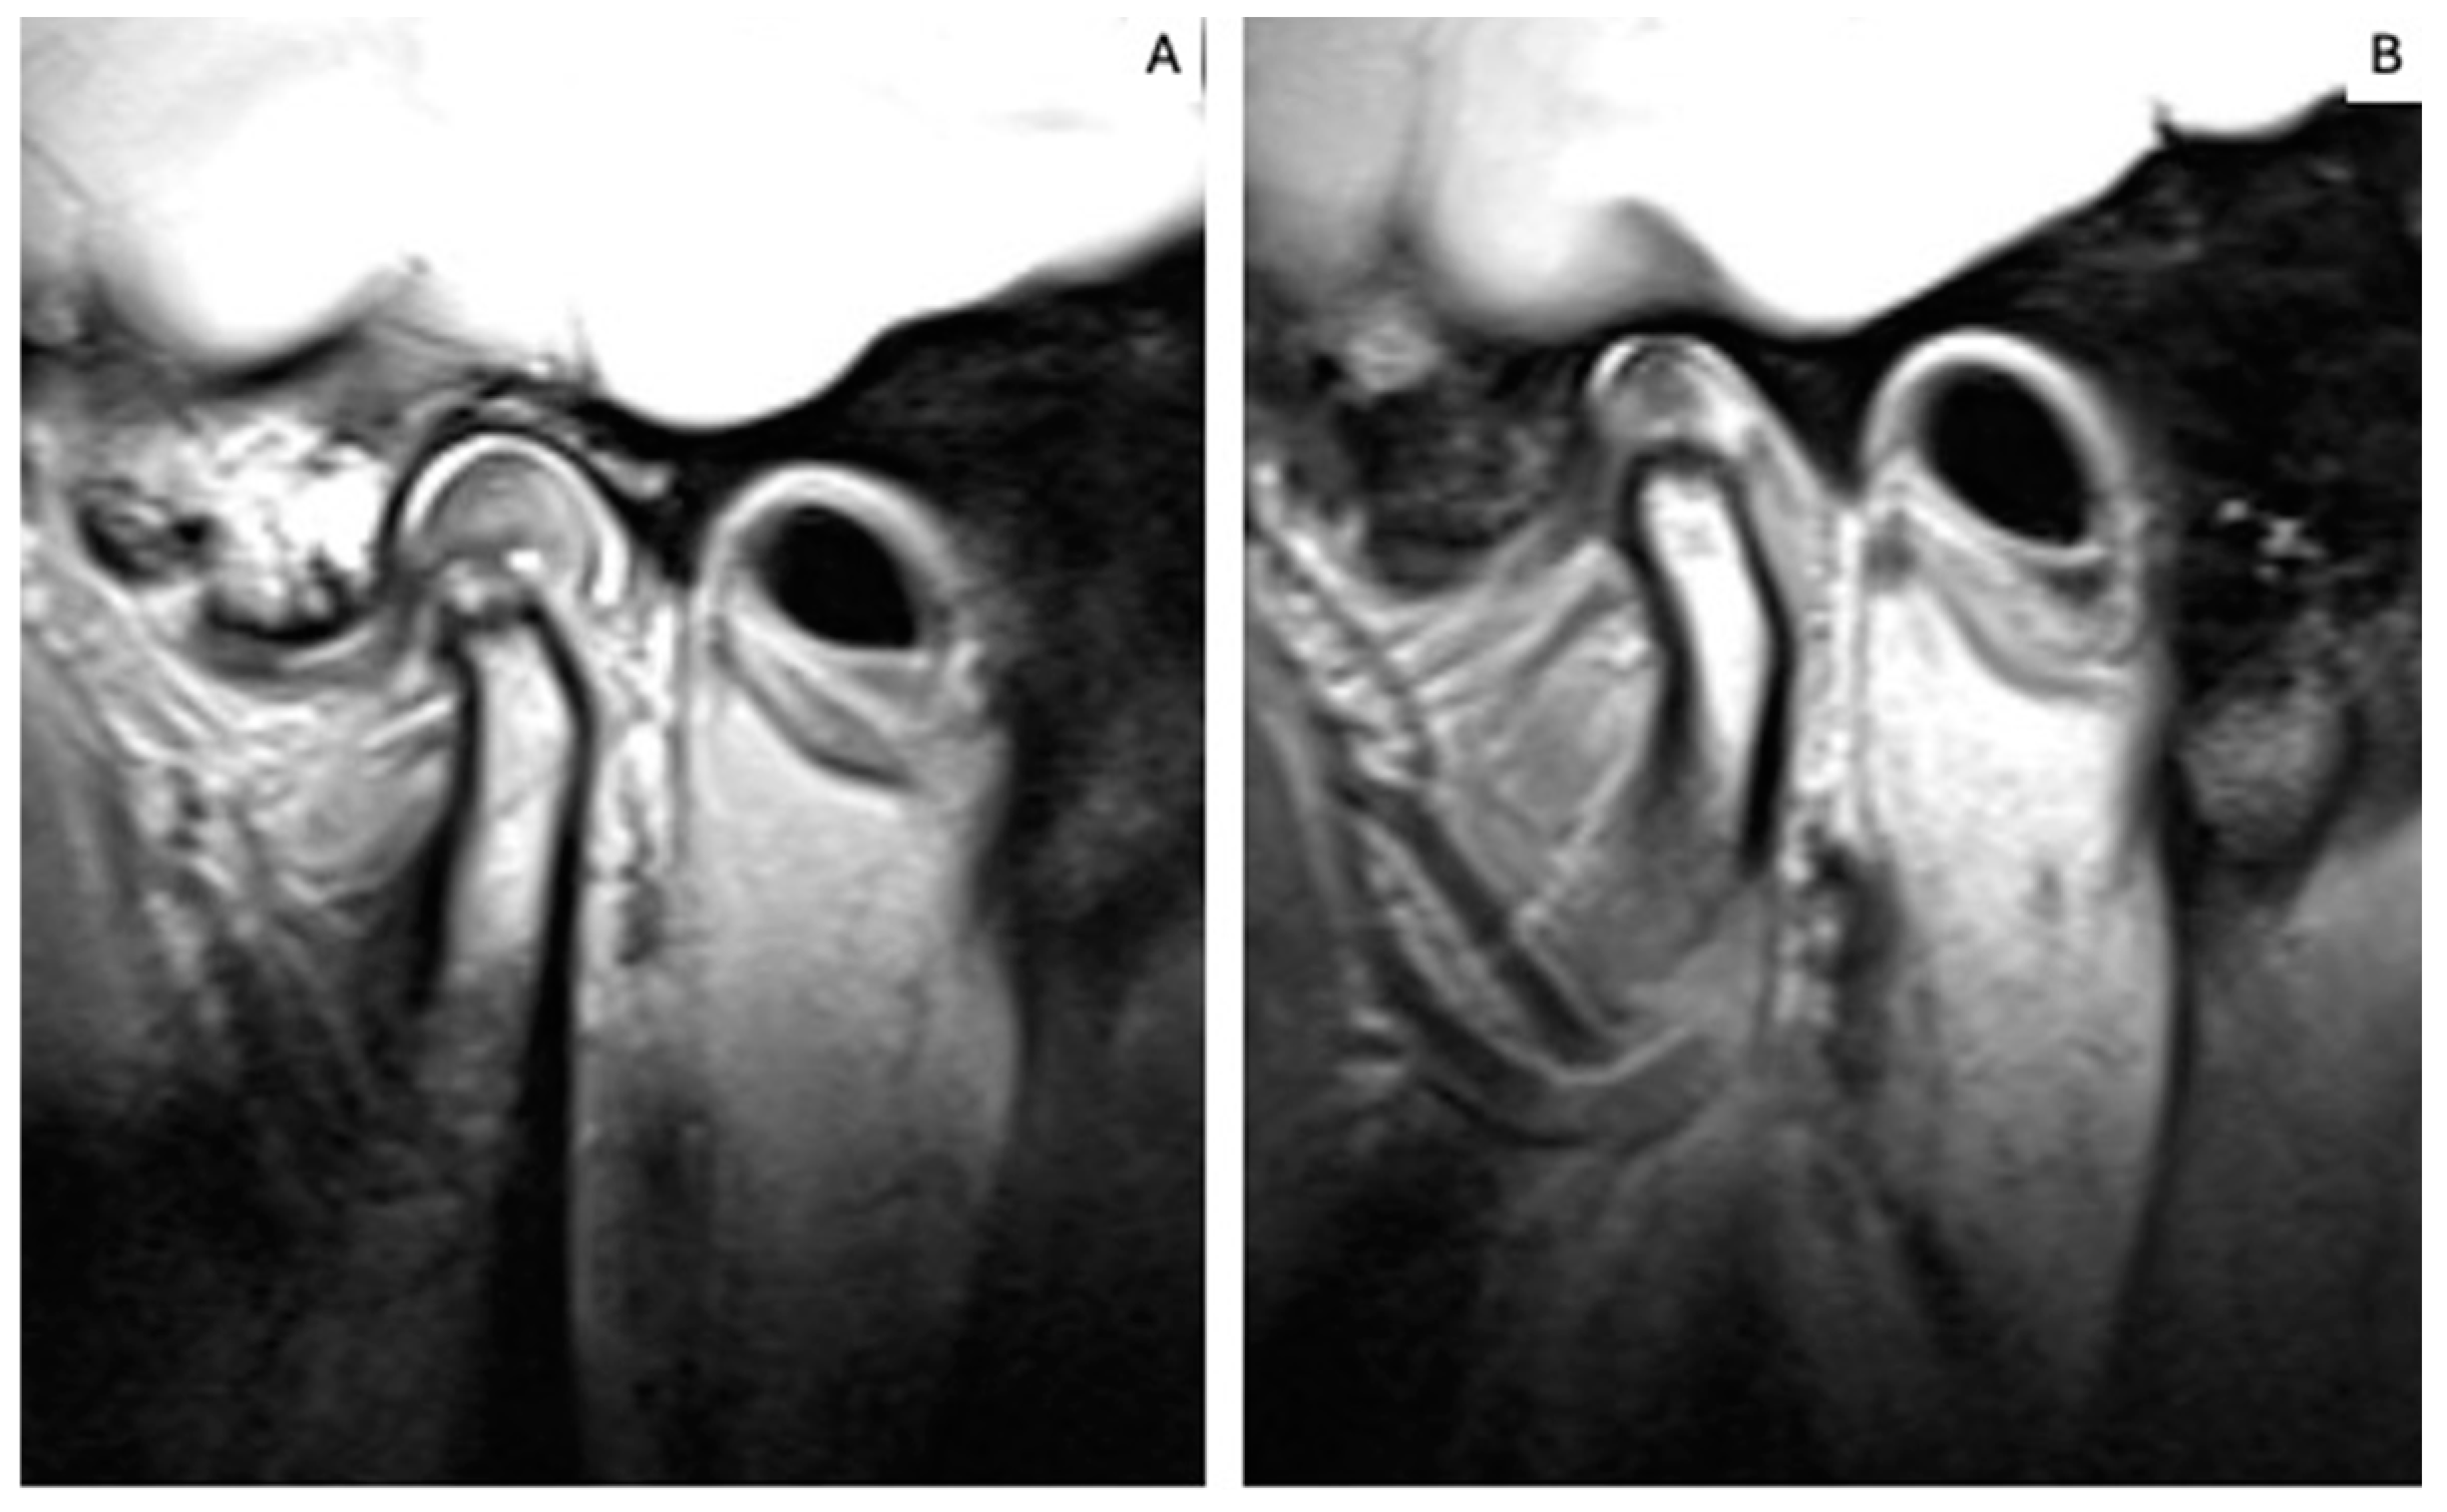

2.5. MRI Analysis